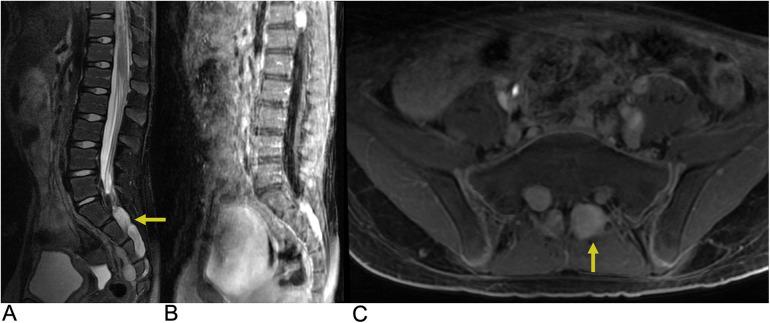

Spinal lesions encompass a diverse range of pathologies, including primary and secondary tumors, infectious processes, vascular malformations, traumatic injuries, and degenerative conditions, each with distinct imaging characteristics crucial for accurate diagnosis and management. Imaging plays vital roles in assessing lesion morphology, anatomical localization, and neurological impact, guiding clinical decision-making and therapeutic planning. This review systematically explores spinal lesions based on their anatomical compartments, highlighting key radiological features and providing a comprehensive reference for radiologists.

脊柱病变包括多种病理情况,包括原发性和继发性肿瘤、感染性病变、血管畸形、创伤性损伤以及退行性疾病,每种病变都具有独特的影像学特征,这些特征对于准确诊断和治疗至关重要。影像学在评估病变形态、解剖定位和神经影响方面发挥着至关重要的作用,指导临床决策和治疗规划。本综述基于解剖分区系统地探讨脊柱病变,突出关键的放射学特征,并为放射科医生提供全面的参考。